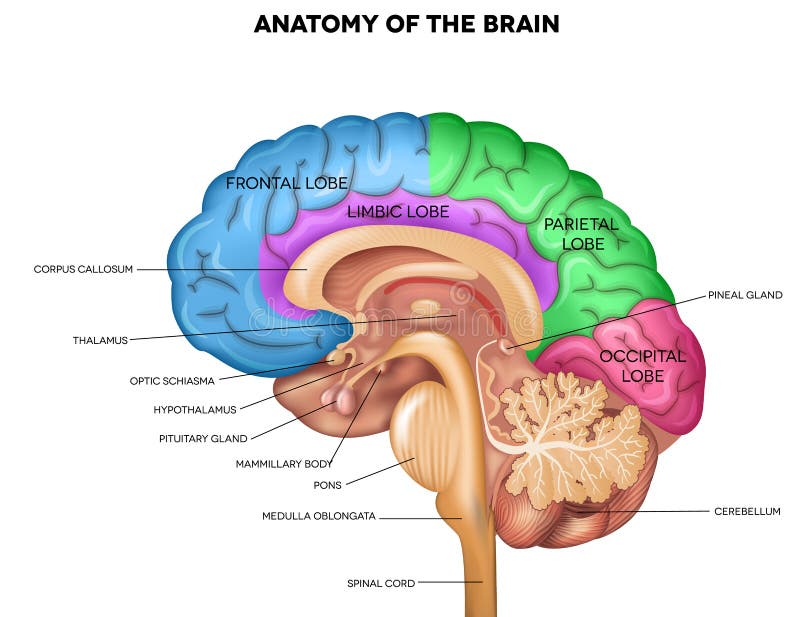

έννοια της τεχνητής νοημοσύνης. άνθρωπος-εγκέφαλος με σύμβολο τεχνητής νοημοσύνης.